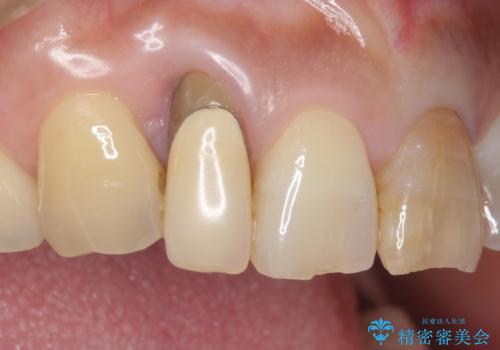

矯正治療後、矮小歯をセラミッククラウンにより理想的な歯の大きさに仕上げました。

クラウンの種類:オールセラミッククラウン スペシャル